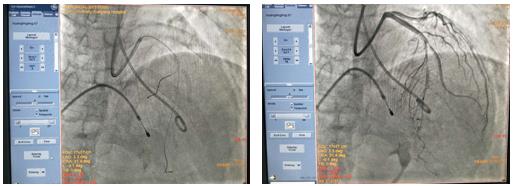

经过反复讨论后,吴栋梁主任医师作为手术指导者,在崔旭辉主任医师团队操作下,最终决定在临时起搏器保护下行冠状动脉造影术及心脏化学消融术。术中通过造影确认第二穿隔支未消融靶血管,测压显示左室压222/13mmHg,主动脉压136/88 mmHg,压力阶差86mmHg。经SPRINTER OTW球囊缓慢注入无水酒精0.8ml,10分钟后复测左心室及主动脉压分别为162/12 mmHg、123/82 mmHg,术后第5天,患者未诉胸闷、气短、心悸等不适,复查心脏彩超示:EF:63%,FS:34%,收缩期左室流出道血流速度增快,Vmax:436cm/s,PG:76mmHg,二尖瓣反流长度5.7cm,面积7.4cm2,三尖瓣反流长度2.3cm,面积1.8cm2;室间隔中上段声像图所见,多考虑为肥厚型心肌病伴左室流出道梗阻;二尖瓣关闭不全(相对性);左房大;左室收缩功能正常,舒张功能减低;彩色血流示:左室流出道湍流,较前速度略减低;二尖瓣反流(中量)、三尖瓣反流(少量),明显改善了患者症状。